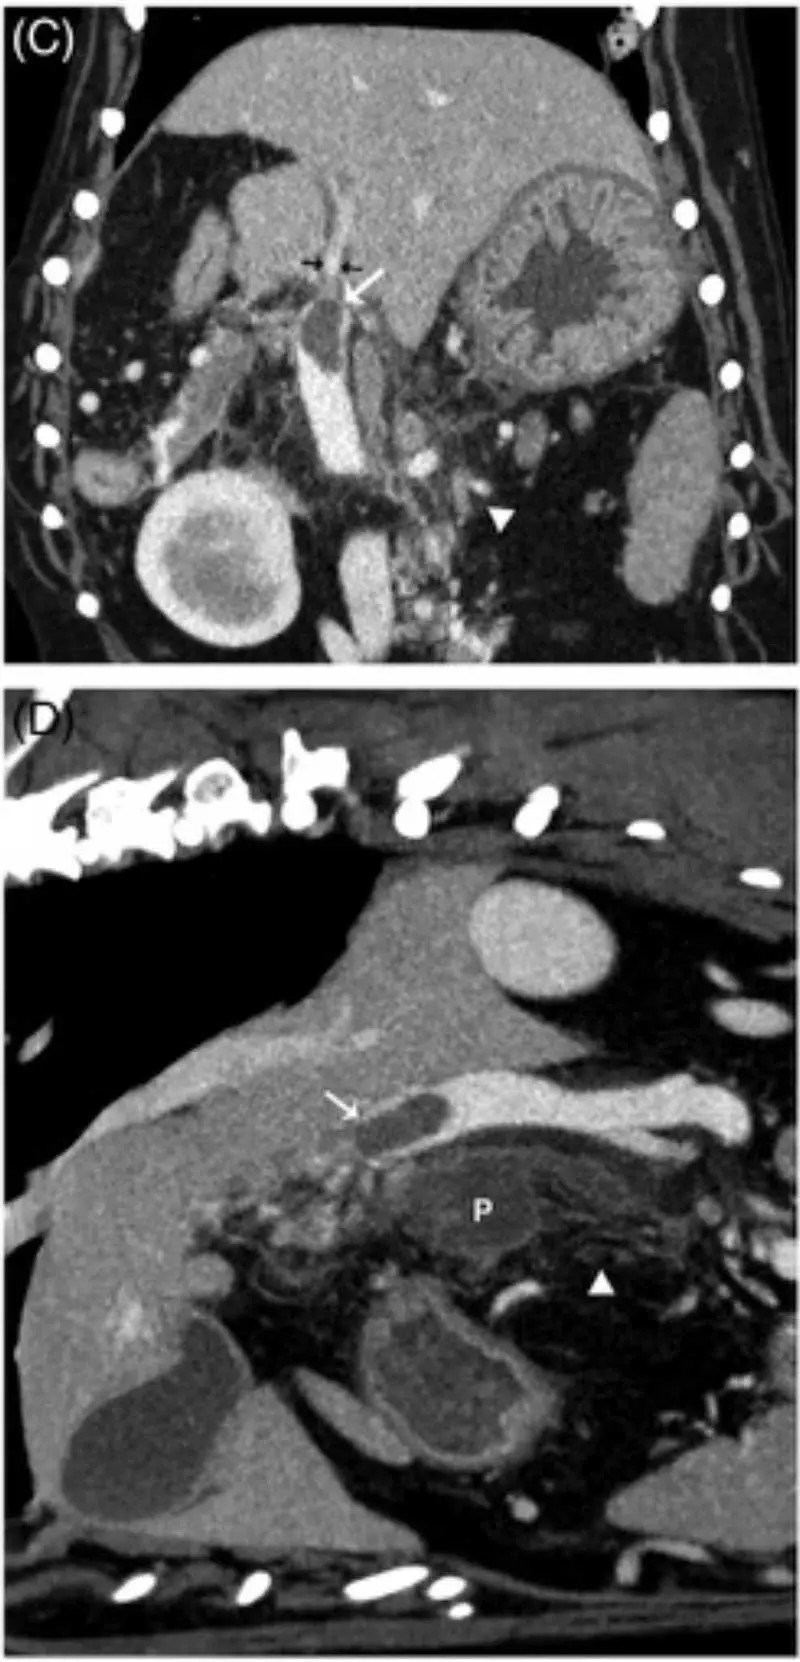

The prevalence of portal vein thrombosis (PVT) was 10 out of 26 and two out of 10 in two CT studies of CAP (Figure 2), and appears associated with increased hospitalisation time, necrosis and mortality18,19. This may be the result of coagulopathy, systemic/regional inflammation or endothelial injury given the proximity. Indeed, pancreatitis is by far the most associated cause of PVT (44%)20,21. Aortic thromboembolism has been reported in at least one case of CAP16.

Heterogenous pancreatic contrast enhancement in people is a signifier of necrosis, a significant prognostic marker (some older evidence suggests this in dogs, too), and CT has been shown as a very sensitive test for this in dogs18. CT is superior to ultrasonography for identifying portal vein thrombosis (present in 10 out of 25 cases; Figure 2), which does have important prognostic importance18,20,21. However, despite all these advantages, CT has not yet been found to be superior to specialist ultrasonography for the actual diagnosis of CAP (for example, pancreatomegaly or mesenteric changes)18.